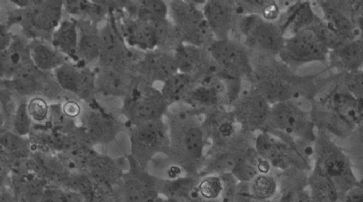

Die Studie der Forscher um Professor Jonathan Tilly vom Massachusetts General Hospital in Boston stösst ein medizinisches Dogma um. Bisher galt: Frauen kommen mit einer festgelegten Zahl von Eizellen zur Welt. Diese nimmt mit dem Alter ab und sie können nicht neu gebildet werden. Das US-Team isolierte aber aus Eierstöcken von Frauen im gebärfähigen Alter Stammzellen und setzte diese in unreife Eizellen ein. Die Stammzellen wurden anschliessend mit einem fluoreszierenden grünen Protein gekennzeichnet und in menschliches Eierstockgewebe eingepflanzt.

Darauf entstanden neue Eizellen, von denen einige grün leuchteten, was darauf hindeutete, dass sie von den Stammzellen abstammten. Andere wiederum leuchteten nicht, was vermuten liess, dass sie bereits zuvor im Gewebe vorhanden waren. Um die Überlebensfähigkeit der Eizellen zu testen, müssen weitere Untersuchungen vorgenommen werden.

Die Studie widerlegt ein medizinisches Dogma. /